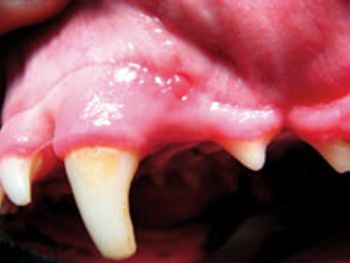

For the last six months, I have been treating a 15-year-old castrated male domestic shorthaired cat with an isolated oral lesion.

When working up inflammatory diseases in the cat, it is important to know that at various stages of the disease process, they can display pathogenic behavior that is similar when compared to one another.